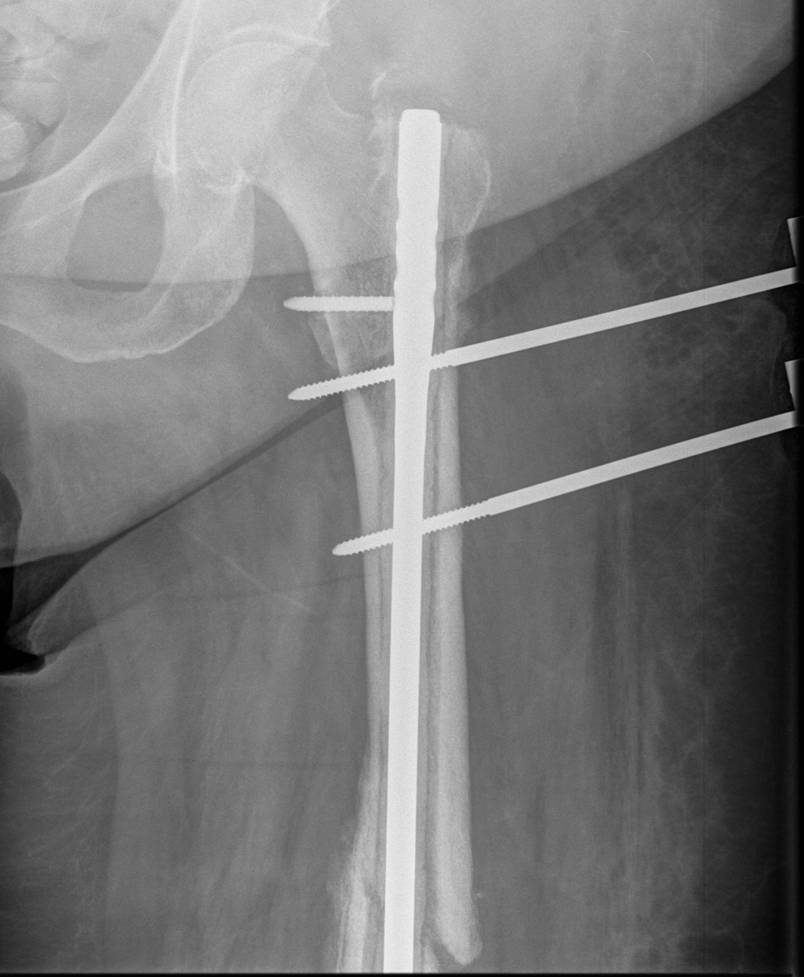

1. External fixation

Indications

- severely contaminated wound

- Damage Control Orthopaedics

- complex femoral fracture with vascular injury

AO Surgery Technique

- safe zone is lateral